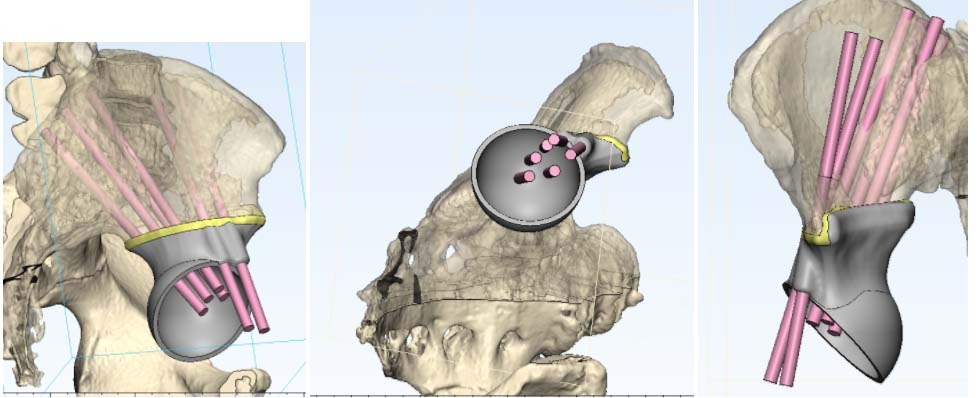

В последние годы все более популярны 3D-принтинговые технологии. Это означает, что на основе данных, полученных от лучевой диагностики, выполняется 3D-моделирование операции и изготовление протеза индивидуально для каждого пациента.

Фото: 3D-моделирование операции